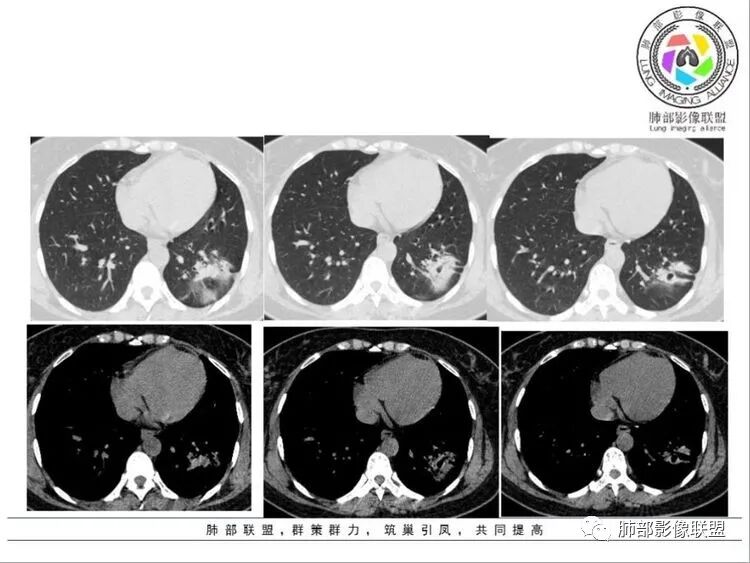

青年女性,丈夫有结核病史病程2月,有咳嗽咳痰症状,胸部ct左上,下叶均有病灶,多发,多态,部分坏死空洞,部分有小叶中心结节,左下主病灶边界清楚,有长毛刺,考虑结核,鉴别腺癌。

左肺下叶实变影,边缘收缩,分叶,毛糙,牵拉胸膜,内可见空泡,空泡壁光滑,边缘可见欠清的磨玻璃影,另左肺上叶下叶有散在小结节,临床37岁女性,咳嗽咳痰两个月,考虑炎性病变:结核,奴卡,放线菌,建议增强及抗炎复查

左肺散在结节片状影,可见空洞,形态相似,考虑炎症可能,隐球?

左肺多发斑片影,小磨玻璃影,多态,部分见空洞,左下病灶边界清楚,有长毛刺,结核接触史,考虑结核,鉴别腺癌。

女,37间断咳嗽,咳痰二个月,贫血,左肺下叶不规则形软组织密度影,边缘见分叶及胸膜牵拉,病灶内见小空洞,洞壁光滑,考虑炎性病变,除外腺癌。

中年女性,咳嗽,白痰,无伴胸痛,无发热,临床实验室检查无特殊。左肺下叶团片影,考虑肉芽肿相关疾病,平扫觉得平行胸膜,周围有晕,未见明显树芽,空洞。考虑隐球菌?鉴别OP样病变。重建看是否平行支气管,如果是,结核也要考虑

中年女性,咳嗽2月,胸部CT可见左肺下叶可见一条片样结节影,内可见坏死和钙化,边缘可见索条影,内有空洞,洞壁光滑,周边及远端肺叶可见散在结节影,考虑结核可能,鉴别腺癌

左肺下叶实变及GGO,边缘平直,向心性弓形凹陷,内见扩张支气管及坏死,邻近胸膜反应性增厚,考虑炎性病变,结核。

左肺下叶病变,长短毛刺,收缩明显,小空洞,胸膜牵拉,周围略模糊GGO,支气管扩张,部分层面欠通畅。炎性病变,隐球菌?炎性肉芽肿?腺癌待排。建议增强及重建。

2.左肺下叶胸膜下团片影及多发小片影,团片影长轴与胸膜平行,周围有模糊的晕,局部平直收缩,支气管近端堵塞,病灶内可见小空洞,空洞内壁光整,邻近胸膜牵拉。